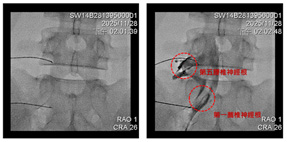

醫師會先透過詳細問診、理學檢查以及影像(例如 X 光或 MRI),確認疼痛確實與神經受壓迫有關後,才會安排此療法。治療的關鍵在於「需要 X 光導引」以及顯影劑確認,因為脊椎周遭多為骨骼,超音波無法穿透,若只靠超音波難以精準抵達神經周圍。因此多數情況仍需具備 X 光設備的醫療院所進行。

本院採用高階雙平面 X 光透視導引進行精準導引注射

透過 X 光導引至正確位置後以顯影劑確認後進行精準治療